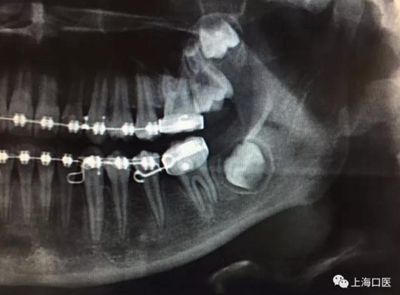

這是上海武廣增正畸工作室接診的一例非常規(guī)拔牙矯治病例,患者女性,初診年齡14歲。LL6殘冠拔除。LL7近中平移取代LL6,我們上傳了該患者一組下頜磨牙近中平移連續(xù)矯治過程的正畸X線片,與正畸界朋友分享。